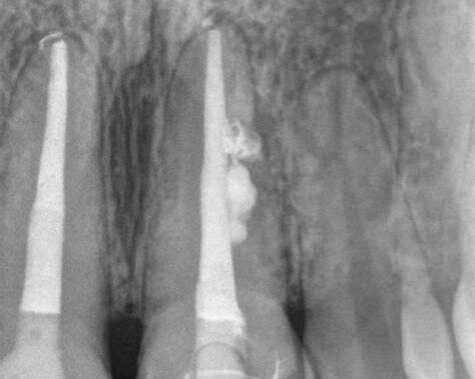

Повторное эндодонтическое лечение — задача, требующая от стоматолога максимальной концентрации и системного клинического мышления. Даже при правильной обработке каналов и адекватной обтурации результат может оказаться непредсказуемым, а пациент вернётся с жалобами на боль или отёк. Важно отметить, что прогнозируемость и результат лечения зависит не только от подготовки каналов, но и от обработки коронковой части зуба.

Клинические данные показывают, что повторное инфицирование зуба при перелечивании формируется чаще всего из-за двух основных ошибок, каждая из которых снижает эффективность лечения и увеличивает риск осложнений.

Ошибка 1. Недостаточно удалённые поражённые ткани коронковой части

Одна из самых частых и недооценённых причин повторного инфицирования при перелечивании — частично сохранённые инфицированные ткани в коронковой части зуба. ((Nair PN. «Apical periodontitis: a dynamic encounter between root canal infection and host response»)

Ошибка 2. Некорректно сформированный доступ из-за неподготовленной структуры полости

Даже при полностью удалённых поражённых тканях эффективность перелечивания может снижаться из-за неподготовленной или неправильно сформированной коронковой части.